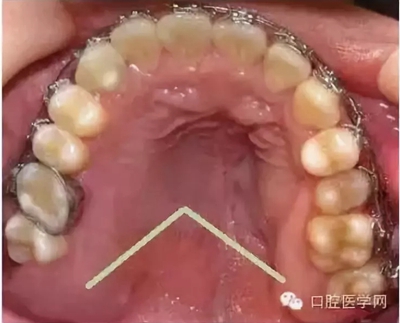

在臨床上我們需要把牙槽骨增生和骨隆突區(qū)分開來,骨隆突是在頜骨上的生理性骨性突起,并不是一個疾病癥狀,也不是疾病的表現(xiàn),比如舌側(cè)骨隆突、上頜骨骨隆突、下頜隆突是在第三磨牙和雙尖牙舌側(cè)的一個生理性突起。